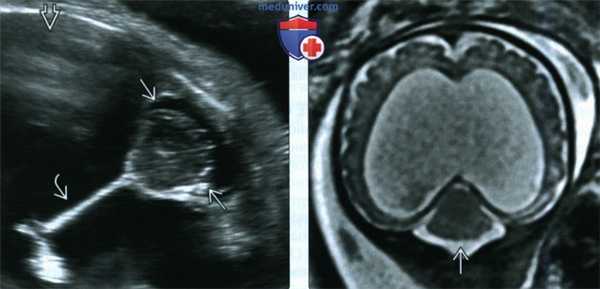

(Слева) Изображения, полученные при УЗИ, МРТ и патологоанатомическом исследовании у пациента с патологией, имевшей неблагоприятный исход. При УЗИ различимы внутрижелудочковый тромб и геморрагический инфаркт. При МРТ на Т1-ВИ в сагиттальной плоскости видна тромбированная мальформация. При МРТ на Т2-ВИ во фронтальной плоскости и при аутопсии визуализируются экстрааксиально расположенный тромб, ишемический очаг в больших полушариях головного мозга и тромб внутри желудочка.

(Справа) При МРТ на Т2-ВИ у плода визуализируется крупная тромбированная МСТМО. Головной мозг выглядит неизмененным. При МРТ на Т1-ВИ у новорожденного (на врезке) подтверждается нормальное строение головного мозга, а также видно уменьшение размеров зоны тромбоза. Неврологической патологии у новорожденного выявлено не было. (Слева) В III триместре беременности при стандартном УЗИ в аксиальной плоскости у плода выявляется типичная тромбированная МСТМО в виде четко очерченного экстрааксиального новообразования. Головной мозг не поврежден. Новорожденный был здоров, рос и развивался нормально.

(Справа) При МРТ на Т2-ВИ у плода визуализируется крупная тромбированная МСТМО. Головной мозг выглядит неизмененным. При МРТ на Т1-ВИ у новорожденного (на врезке) подтверждается нормальное строение головного мозга, а также видно уменьшение размеров зоны тромбоза. Неврологической патологии у новорожденного выявлено не было.